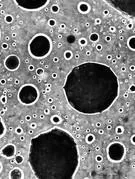

La coloscopie pour rechercher des polypes

Suite à un toucher rectal ou à un test de dépistage, le médecin peut avoir un doute sur un éventuel risque de cancer du côlon. Il recommande alors une coloscopie. Cet examen approfondi de l’intestin est réalisé par endoscope, en ambulatoire, sous anesthésie locale ou générale. Il permet un bilan complet.

Pourquoi ? « Pour voir s'il y a ou non des polypes, c'est-à-dire des petites tumeurs dans le côlon. Si la réponse est oui, le ou les polypes sont retirés au cours de l'examen pour éviter qu'ils ne dégénèrent s'il sont bénins, et pour les analyser afin de savoir si on est ou non en présence d'un cancer », explique  le Pr Pierre Michel, gastro-entérologue.